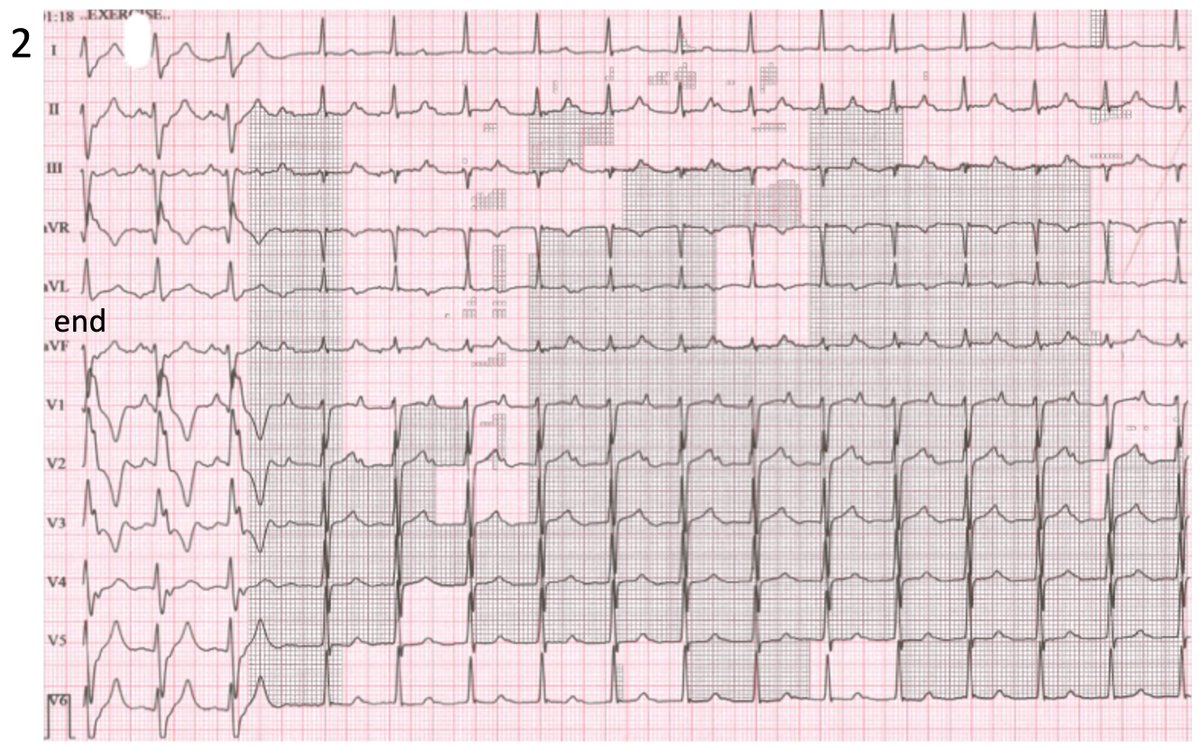

2 ECGs recorded during an ETT for the investigation of palpitations. 1st ECG shows the start of a change in the ECG pattern and 2nd ECG shows the end. What’s happening?